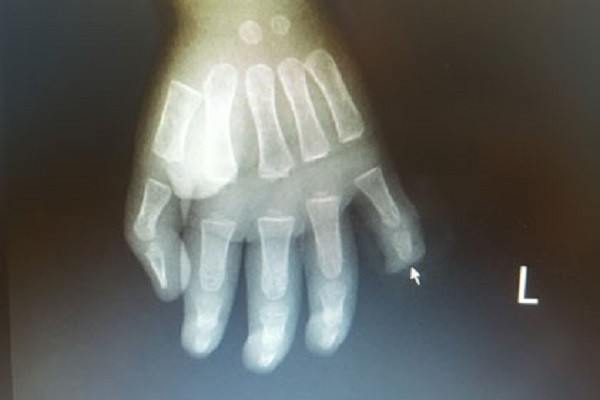

Theo đó, cháu Nguyễn Viết Q. 17 tháng tuổi (trú tại Đông Triều - Quảng Ninh) nhập viện Việt Nam Thụy Điển Uông Bí cấp cứu ngày 19/5 với vết thương đứt rời đốt thứ 3 của ngón út bàn tay trái, chảy rất nhiều máu.

Kíp cấp cứu từ Khoa Chấn thương - Chỉnh hình & Bỏng của bệnh viện đã tiến hành cầm máu, phẫu thuật tạo mỏm cụt ngón tay cho trẻ. Hiện sức khỏe của bé đã ổn định, tuy nhiên trẻ vĩnh viễn mất đi đốt trên cùng của ngón tay út.